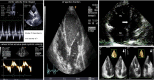

Useful echocardiographic parameters. LV, left ventricle; RV, right ventricle; RA, right atrium.